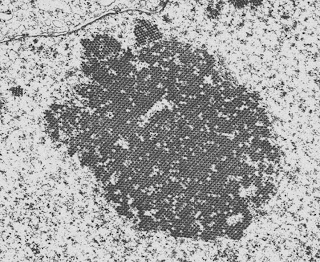

A paper was just published in KI which looked at the effect of co-administration of cisplatin and cilastatin in rats. The rats were given a single dose of cisplatin and those that received cilastatin had significantly less uptake of cisplatin into the renal cortex and lesser manifestations of renal toxicity. Interestingly, the uptake into the medulla was not affected and the half-life of cisplatin was longer than in the controls. Because dihydropeptidase is specific to the proximal tubule, it did not affect uptake into cancer cells and so anti-tumor activity was preserved. Cisplatin toxicity is the bane of the life of nephrologists working in major cancer centers because, once it has set in, there isn’t much that you can do and it limits the amount of treatment that these patients can get for their tumors. This is a preliminary study and we can’t say that this is the panacea for cisplatin nephrotoxicity but it certainly is promising as well as being a fascinating insight into the mechanisms of renal damage caused by cisplatin.